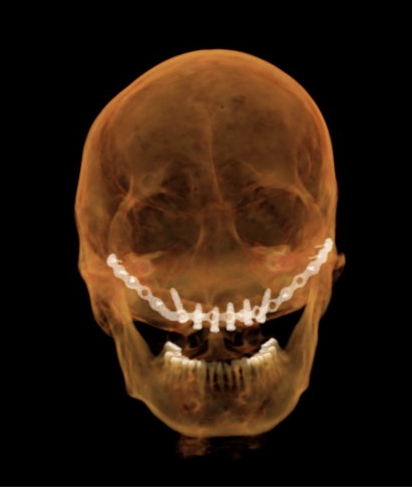

术后CT

在手术中,李奇副主任医师顺利在患者颅骨外固定手术标记物,拍摄螺旋CT后确认固定标志物的钉子穿透颅骨第一层骨皮质到达第二层骨髓腔,位置精准。麻醉科王智主任在患者清醒状态下进行了经鼻纤支镜麻醉,仅用时不到15秒一次成功,保证患者插管时血压和心率平稳。随后,将术前CT、术前规划、患者颅颌骨位置及机器人机械臂进行配准标定。杜良智主任团队通过机器人亚毫米级的定位方式,精准控制避开固定腓骨的钛板和钛钉,用时三小时,顺利将6颗种植体植入规划位置,确保种植体按预设位置准确就位,为后期修复上颌缺失牙列打下基础。